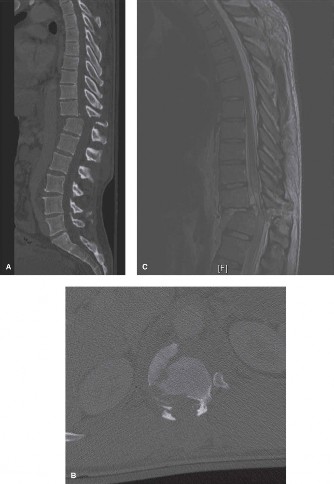

Radiographic and Computed Tomography Evaluation

Initial trauma radiographs demonstrated a loss of anterior and middle column height at L1, with a focal kyphotic deformity. However, plain films are vastly insufficient for definitive surgical planning in thoracolumbar trauma. A high-resolution, fine-cut Computed Tomography (CT) scan of the entire spine was obtained. The CT images confirmed an L1 burst fracture with severe comminution of the vertebral body. Sagittal and axial reconstructions revealed 50% canal compromise secondary to a large retropulsed bone fragment originating from the posterosuperior aspect of the L1 vertebral body. Furthermore, the CT demonstrated 25 degrees of segmental kyphosis measured from the superior endplate of T12 to the inferior endplate of L1.

A critical finding on the axial CT slices was a vertical, split fracture propagating through the L1 lamina. This is a highly significant morphological feature. A lamina fracture in the setting of a burst fracture with retropulsion strongly correlates with a dural tear and potential entrapment of the cauda equina nerve roots. When the vertebral body bursts posteriorly, the pedicles are driven outward, and the lamina fractures as the spinal canal attempts to expand to accommodate the retropulsed bone. If the dura is lacerated, nerve roots can herniate through the dural defect and become incarcerated in the laminar fracture site.

The MRI, particularly the Short Tau Inversion Recovery (STIR) and T2-weighted sagittal sequences, provided the definitive diagnosis. The images demonstrated profound hyperintensity and discontinuity of the ligamentum flavum, the interspinous ligaments, and the supraspinous ligaments at the T12-L1 level. The facet joint capsules were also disrupted, indicated by fluid within the joints. This complete failure of the PLC means the posterior tension band is gone. Regardless of the bony parameters, this spine cannot resist physiological flexion loads. If treated non-operatively, this injury will inevitably lead to progressive kyphosis, delayed neurological deficit, and intractable pain.

Complex Surgical Decision Making and Classifications

To standardize our decision-making, we utilize the Thoracolumbar Injury Classification and Severity (TLICS) score. This system evaluates three distinct categories: morphology of the injury, integrity of the posterior ligamentous complex, and neurological status. For our patient, the morphology is a burst fracture, yielding 2 points. The neurological status is intact, yielding 0 points. However, the MRI confirmed definitive disruption of the PLC, yielding 3 points. The total TLICS score is 5. A score of 4 or greater is a definitive indication for surgical intervention.

We also apply the AOSpine Thoracolumbar Classification System. This injury is classified as a Type A4 (complete burst fracture involving both endplates) combined with a Type B2 (posterior tension band disruption / bony or ligamentous failure). The presence of the B2 component dictates the need for posterior stabilization. The decision now pivots to the type of surgical intervention. Options include a custom-molded thoracolumbar orthosis (TLSO), anterior corpectomy and fusion, laminectomy without fusion, or instrumented posterior fusion.

Therefore, the gold standard, definitive treatment for this specific injury pattern is an instrumented posterior fusion. By placing pedicle screws above and below the fractured level, we can utilize ligamentotaxis to partially reduce the retropulsed fragment, restore vertebral height, and rigidly recreate the posterior tension band. This is where the concept of preventing Adjacent Segment Degeneration (ASD) enters our operative planning. If we fuse this patient in 25 degrees of segmental kyphosis, we will create a flatback deformity. The adjacent unfused segments (particularly L2-L3 and L3-L4) will be forced into hyperlordosis to compensate, leading to accelerated facet arthropathy, disc degeneration, and eventual adjacent segment failure. Our surgical goal is not just stabilization, but the meticulous restoration of regional sagittal alignment.

A standard midline posterior approach is utilized, extending from T11 to L3 to allow for a "two-up, two-down" construct (T11, T12, L2, L3). Subperiosteal dissection is performed meticulously to expose the spinous processes, laminae, and transverse processes. Care is taken at the L1 level; given the known lamina fracture, the dissection here must be exceedingly gentle to avoid plunging into the spinal canal and injuring the dura or neural elements.

Pedicle screws are placed using anatomic landmarks and fluoroscopic guidance (or robotic/navigation assistance if available). At the thoracolumbar junction, the entry point is typically at the intersection of the pars interarticularis, the midpoint of the transverse process, and the lateral border of the superior articulating facet. We place 6.5mm or 7.5mm polyaxial pedicle screws at T11, T12, L2, and L3. We generally avoid placing screws into the fractured L1 pedicles unless the fracture pattern specifically allows for short-segment fixation with index-level screws, but in a highly comminuted A4 burst, bypassing the index level provides a more robust biomechanical construct.

The final, critical step is rod contouring and reduction. To prevent future Adjacent Segment Degeneration, the titanium rods must be contoured to match the patient's ideal pelvic incidence and lumbar lordosis. The rods are seated into the proximal screws. Using reduction towers and careful cantilever forces, the rods are seated into the distal screws. This maneuver actively corrects the 25-degree kyphotic deformity, restoring normal sagittal alignment. The construct is cross-linked if necessary, and a robust posterolateral decortication and bone grafting (using local autograft from the laminectomy and allograft) is performed to ensure a solid arthrodesis.